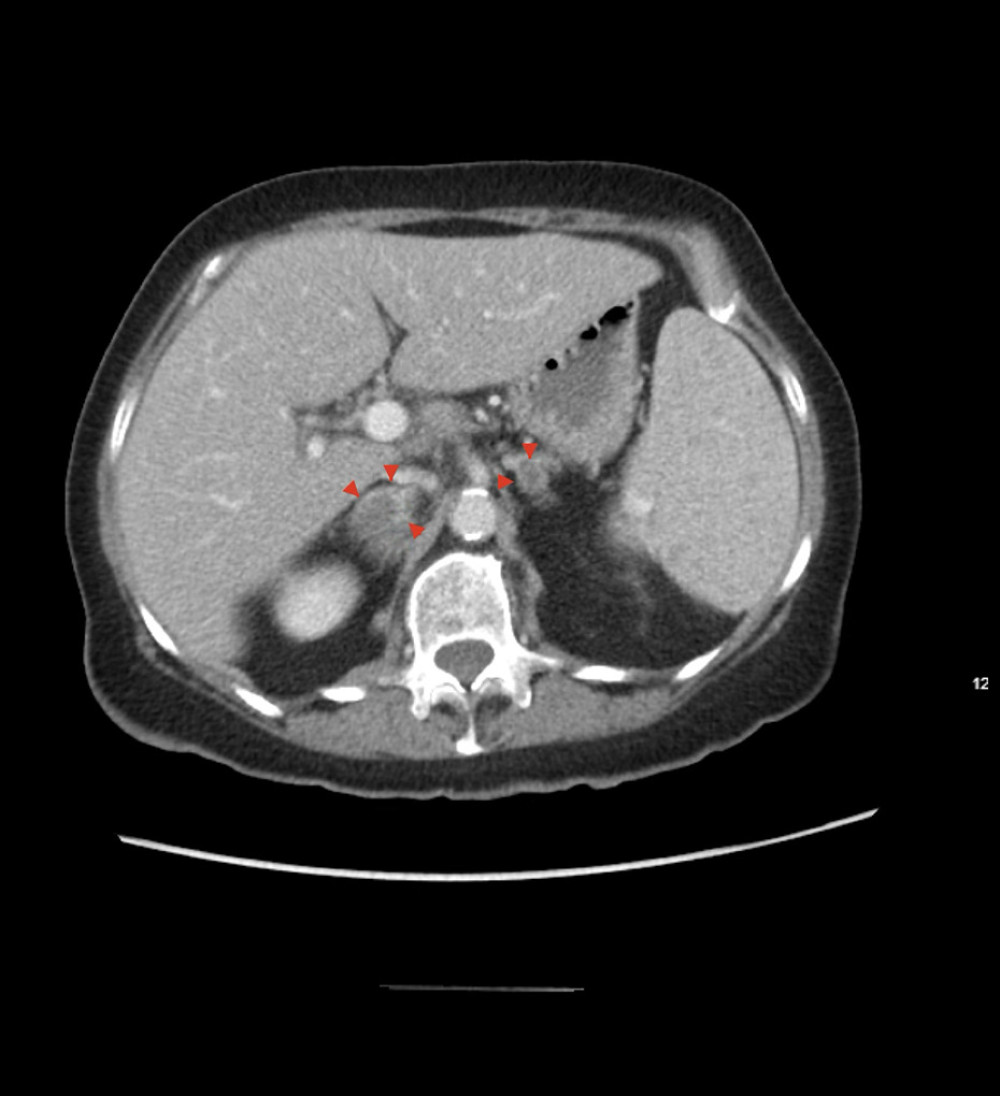

CASE REPORT: We report a case of a patient who presented with shortness of breath, nonproductive cough, low-grade fevers, and weight loss, who received a diagnosis of disseminated histoplasmosis, with an underlying immunocompromised state. Due to the ineffectiveness of initial management with empiric antibiotics, imaging with computed tomography (CT) of the chest was done, revealing miliary disease, and tuberculosis was first in the differential diagnosis. She had a positive histoplasma urine antigen, and bronchial alveolar lavage fluid tested positive for histoplasma antigen, confirming miliary histoplasmosis. Her CT of the abdomen/pelvis showed multiple lesions in the spleen and adrenal glands bilaterally, concerning for disseminated histoplasmosis, which was treated with amphotericin B, followed by itraconazole.

Figure 2. (A–D) Bronchoscopy images showing minimal, thin, and white secretions marked with a red arrow in the trachea, main carina, left lung, and right lung. Bronchoalveolar lavage was performed in the right middle lobe.  Figure 3. Axial plane view of computed tomography of the abdomen and pelvis with contrast image showing bilateral adrenal nodules. Red arrows depict right adrenal nodule measuring 3×1 cm and left adrenal nodule measuring 9 mm.

Figure 3. Axial plane view of computed tomography of the abdomen and pelvis with contrast image showing bilateral adrenal nodules. Red arrows depict right adrenal nodule measuring 3×1 cm and left adrenal nodule measuring 9 mm.  Figure 4. Axial plane view of computed tomography of the chest with contrast image showing a majority of the previously seen diffuse pulmonary nodules have resolved, compatible with inflammation/infection. Yellow arrows depict the same.

Figure 2. (A–D) Bronchoscopy images showing minimal, thin, and white secretions marked with a red arrow in the trachea, main carina, left lung, and right lung. Bronchoalveolar lavage was performed in the right middle lobe. Figure 3. Axial plane view of computed tomography of the abdomen and pelvis with contrast image showing bilateral adrenal nodules. Red arrows depict right adrenal nodule measuring 3×1 cm and left adrenal nodule measuring 9 mm.

Figure 3. Axial plane view of computed tomography of the abdomen and pelvis with contrast image showing bilateral adrenal nodules. Red arrows depict right adrenal nodule measuring 3×1 cm and left adrenal nodule measuring 9 mm. Figure 4. Axial plane view of computed tomography of the chest with contrast image showing a majority of the previously seen diffuse pulmonary nodules have resolved, compatible with inflammation/infection. Yellow arrows depict the same.